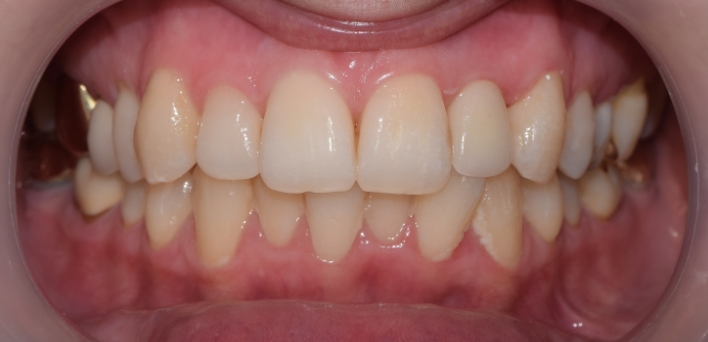

임플란트 : 손 ** 님 (50대)

치아가 있다는게, 아직도 정말 꿈만 같아요.

Before Before

2020.02.30

After After

※ 더서울치과의원은 의료법을 준수하며 위 케이스는 실제 환자의 동의를 얻은 사례로 치료 전, 후가 동일한 환경에서 촬영되었습니다.

환자 케이스에 따라 부작용이 발생할 수 있습니다. 이 부분은 의료진의 충분한 상담과 체크를 통해 예방하고 줄일 수 있습니다.

[임플란트 부작용] 수술 후 관리가 소홀할 경우 출혈, 주위염 등의 부작용이 발생할 수 있어 구강 위생을 철저히 유지하고, 정기적인 검진을 통해 상태를 점검하는 것이 중요합니다.

환자 특징

환자 특징01무치악 상태

환자 특징02수년간 무치악으로 지내심

임플란트가 불가능할것이라

생각하고 내원

위, 아래 6개씩 식립

디지털 풀아치 임플란트